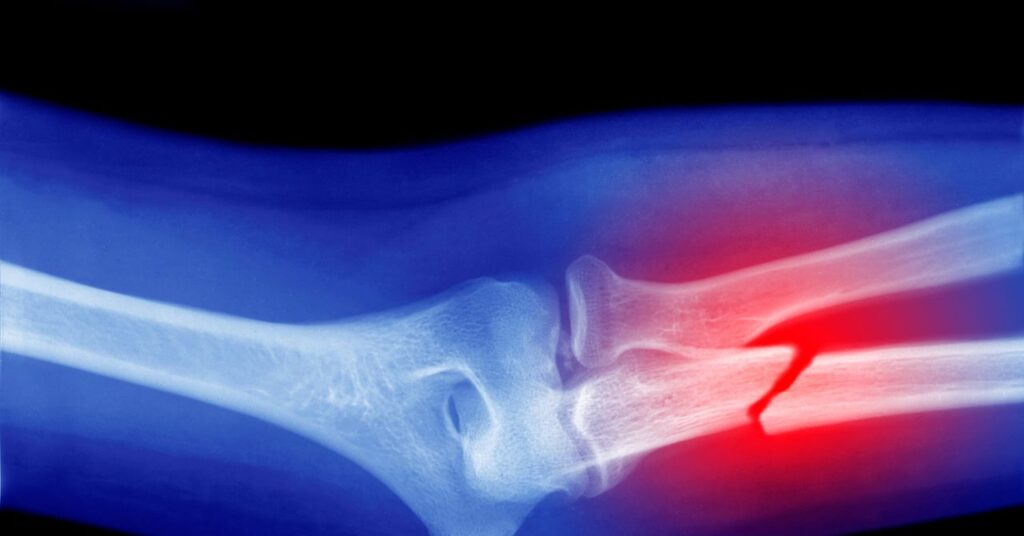

Throughout your life, your bones are replenished. Osteoporosis is a condition where this process goes wrong, with the breakdown of bone outstripping the rate at which it is replaced. This leads to bones weakening over time and becoming more likely to fracture. The condition has many risk factors—age, sex, medications, diet, smoking and drinking, and genetics are all known to influence it—with the disease developing slowly over time. Often people don’t realize they have the condition until they break a bone.

When then looking at animal studies, the researchers found that the accumulation of microplastics in the body decreases the white blood cell count—which is suggestive of alterations in bone marrow function. In addition, these animal studies suggested that the impact of microplastics on osteoclasts may be associated with deterioration of bone microstructure and the formation of irregular structures of cells, increasing the risk of bone fragility, deformities, and fractures.